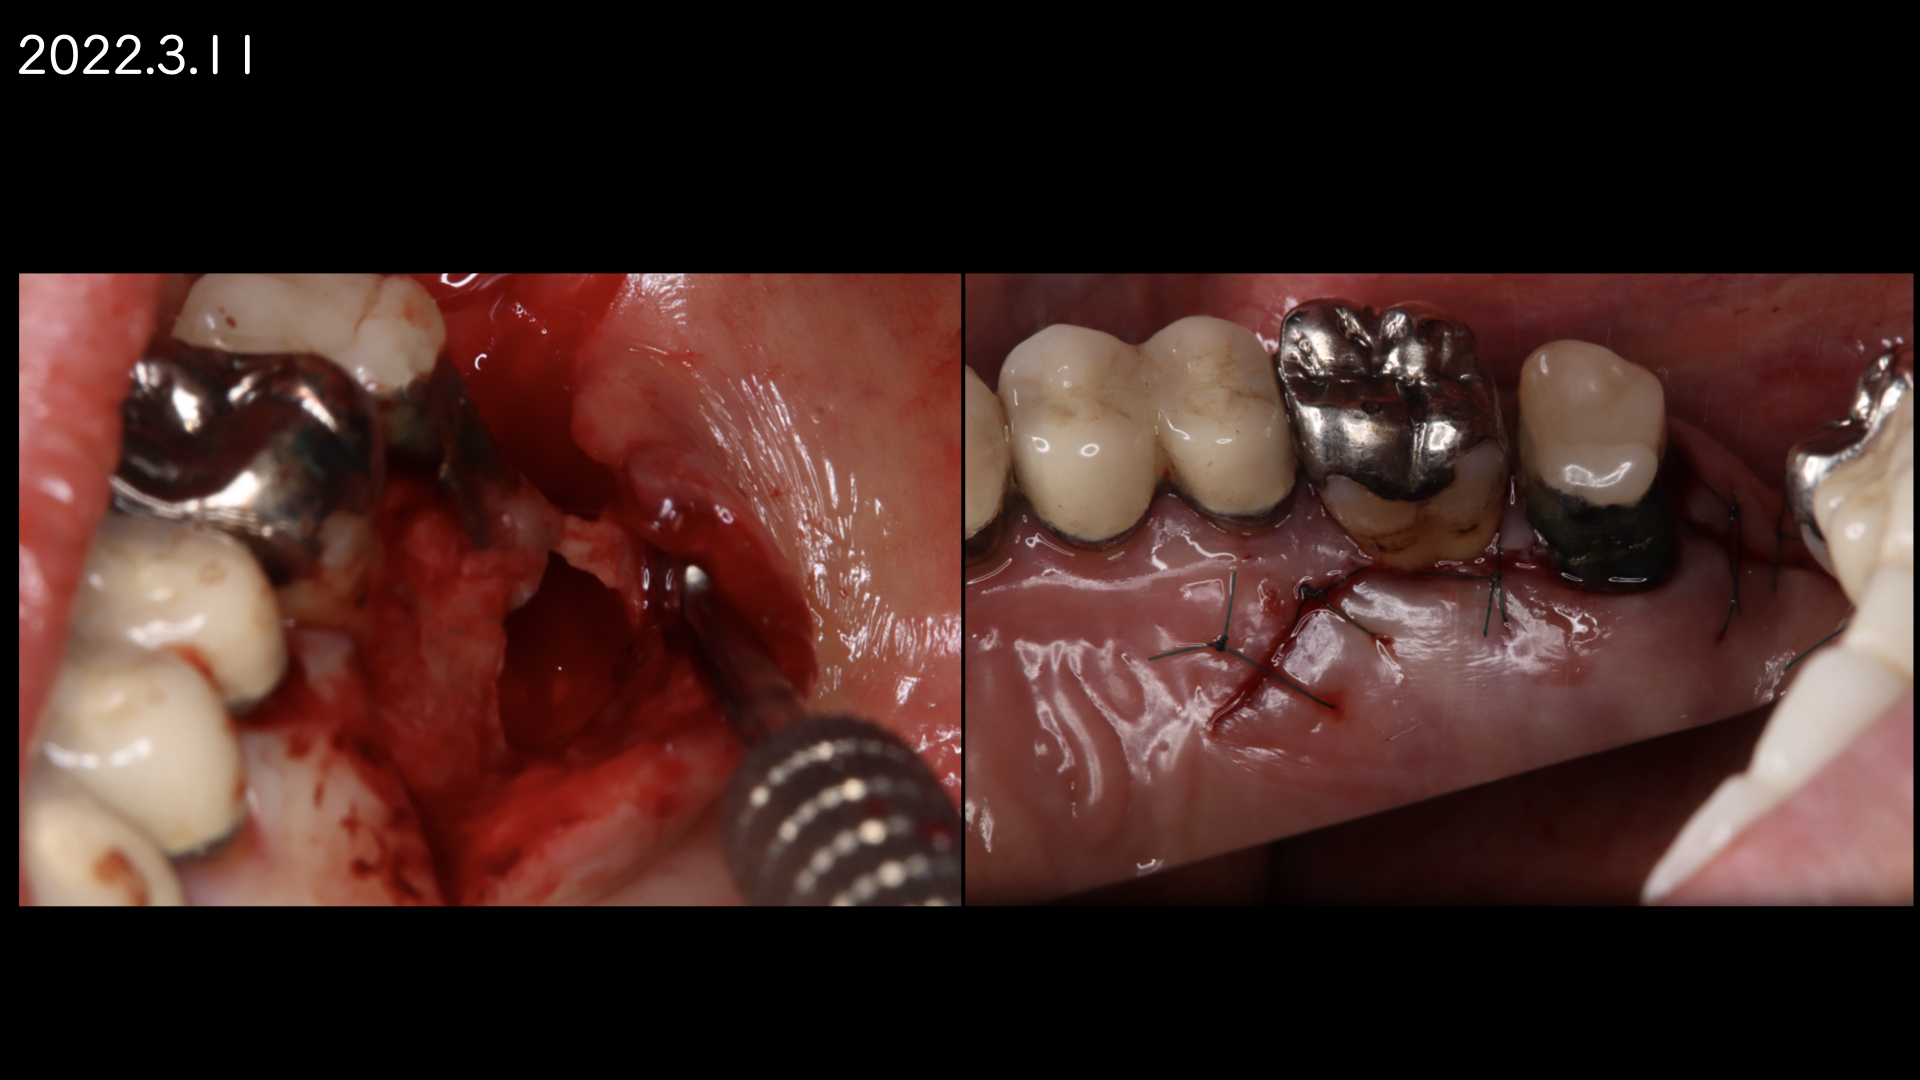

患者さんの都合もあり1年後に歯根端切除(外科的歯内療法)をおこなうことになりました。

術後、歯根は骨に囲まれるように治癒にしました。